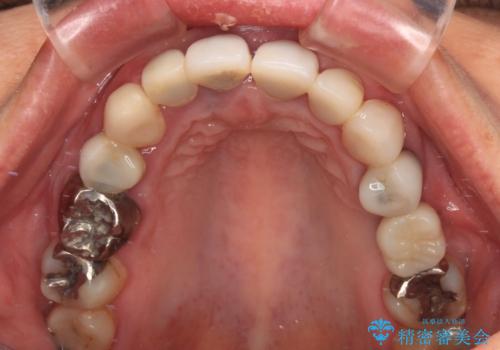

- 前歯が土台ごと外れてしまうとのことで来院された患者様です。

問題の歯は、歯根まで破折している状態で、抜歯が必要と判断されました。

周辺の歯は20年以上前に装着したクラウンで、色合いや形態が気になっているとのことで、オールセラミックブリッジにて補綴治療を行うこととしました。

ところが、土台となる歯は、十分な維持力が得られないほど歯ぐきの中に埋もれており、歯ぐきも腫れやすい状況でした。

まずは土台の歯を引っぱり出し、外科処置により歯肉の状態を十分に整えた上で、オールセラミッククラウンにて補綴することとしました。

元々の土台は歯肉の中に埋もれており、歯肉が著しく腫れている状態だったため、歯を引っぱり出すこととしました。引っぱる期間は2ヶ月ほどで済み、その後歯周外科処置を行ったことで、土台周りの歯肉は腫脹のない健全な状態へと改善されました。